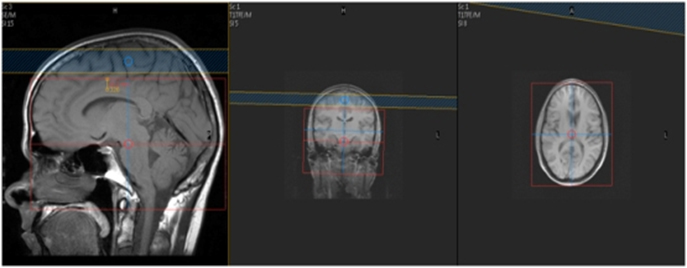

Plane Weighting Mode Slice Gap FOV Notes

COW 3D TOF 3D FFE 1mm 0mm 20cm MIP COW, Right, Left and Posterior

Special Technologist Instructions:

Right Click on the thumbnail and choose “VolumeView”

In the options on the top of the screen, Choose “Cut Outside”

Click on the (Star Man) icon to Generate Series

Choose the Pencil to begin Mipping your image

Orientation = "Coronal"

Stack Type = “Radial”

Radial Axis = “FH” (foot to head)

Number Of Projections = 18

Radial Angle = 10

Series Name = “COW”/”Right”/”Left”/”Basilar” whichever you are working on

Click on “Generate” to create your MIP

MRA Brain WO Protocol Image1